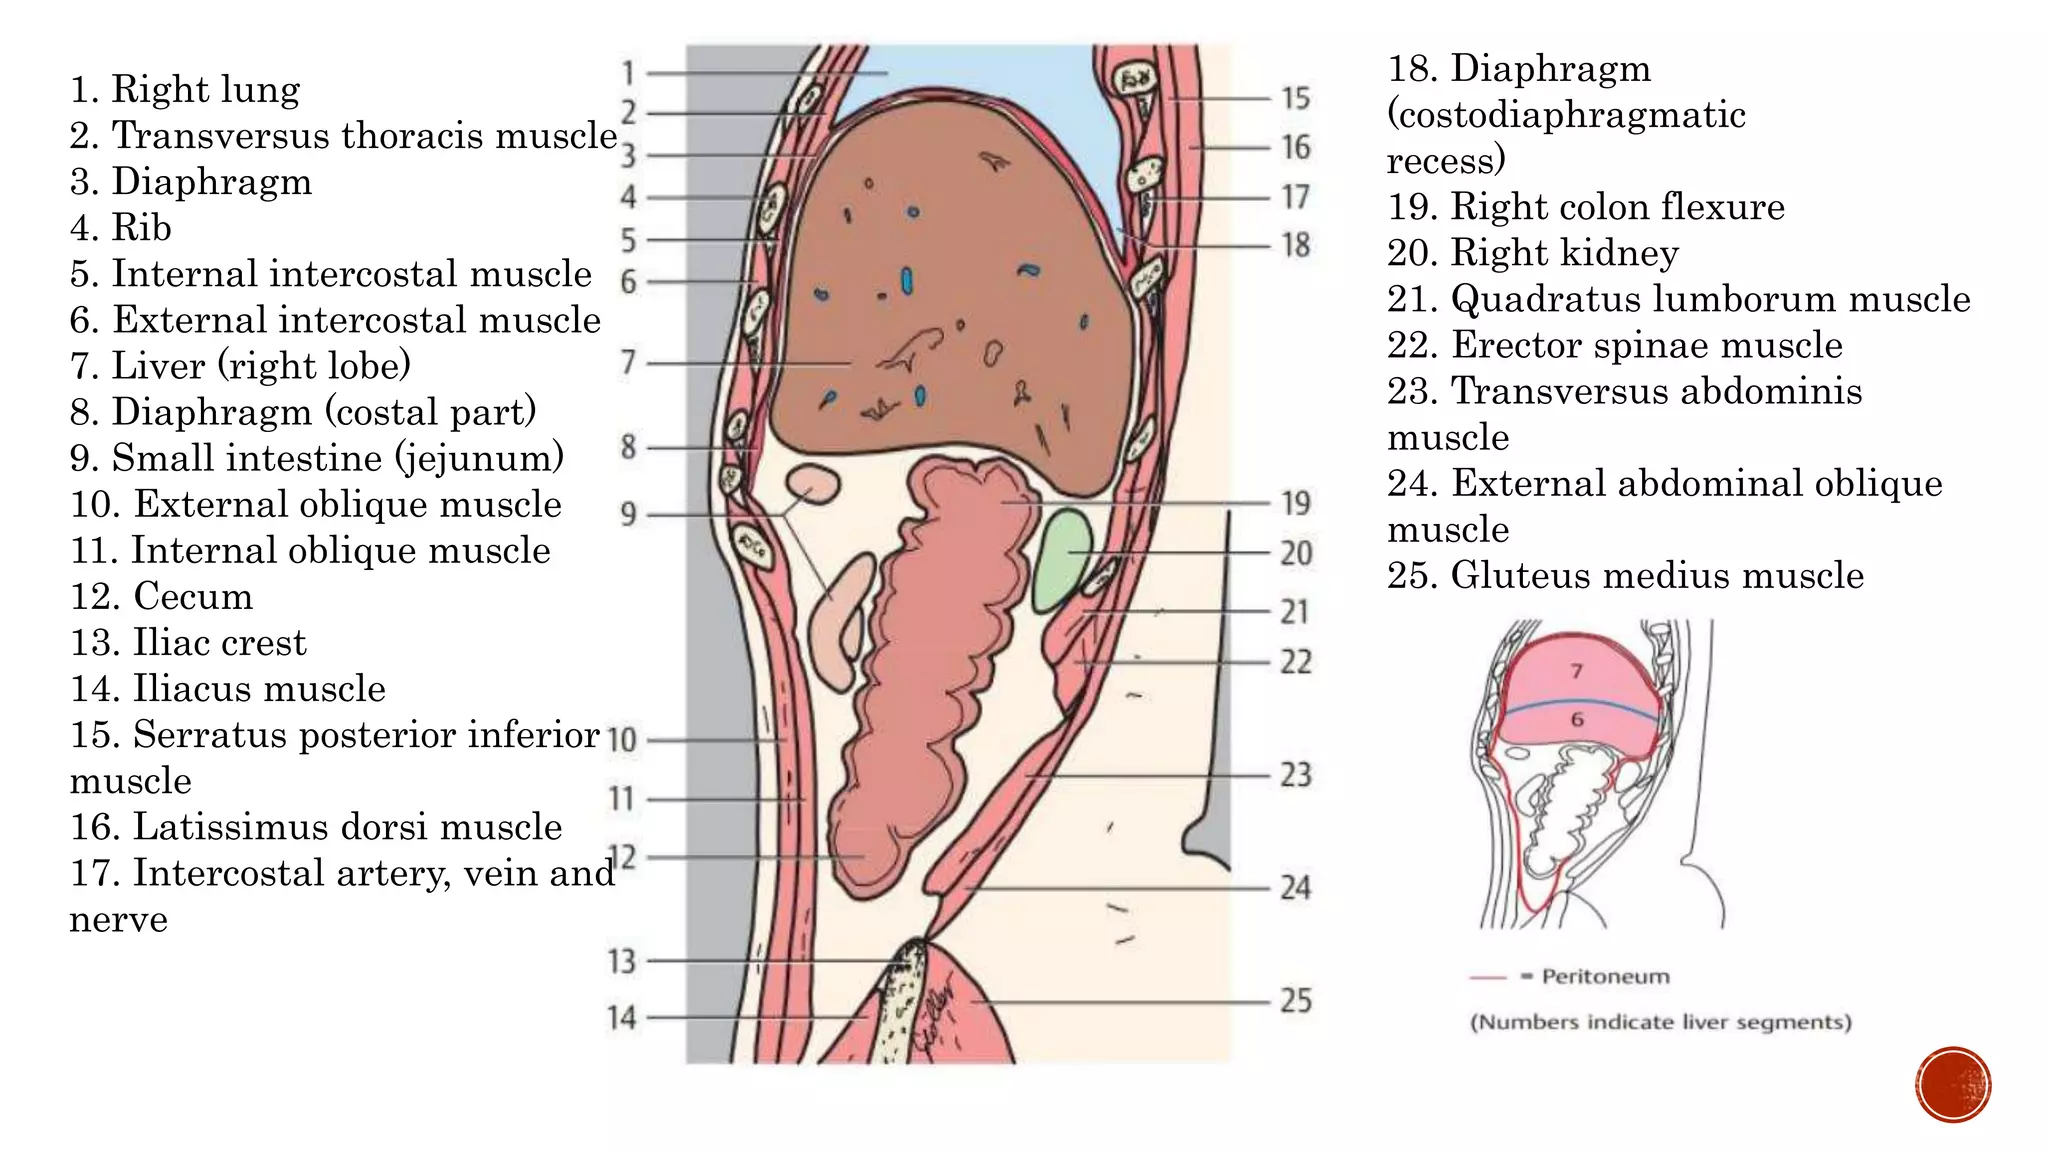

The document describes the anatomy of the abdomen and pelvis region of the human body. It lists over 40 structures and their locations, including major organs like the liver, kidneys, intestines, blood vessels and muscles of the abdominal wall and pelvis. The structures are grouped into sections focusing on different anatomical areas like the abdomen, retroperitoneum, pelvis and gluteal region.